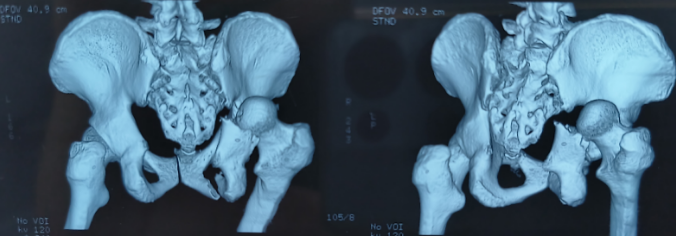

骨盆骨折术前影像

患者入院后,医务人员立即给予股骨髁上骨牵引术,牵引下不仅利于脱位的股骨头复位,而且制动后有利于缓解疼痛,并完成各项辅助检查及化验。经两天牵引,双下肢已等长。经CT平扫+三维重建显示:髋关节脱位已纠正,右侧髋臼后壁粉碎性骨折,骨碎块陷入关节腔中,需要行右侧髋臼骨折切开复位钢板内固定术。